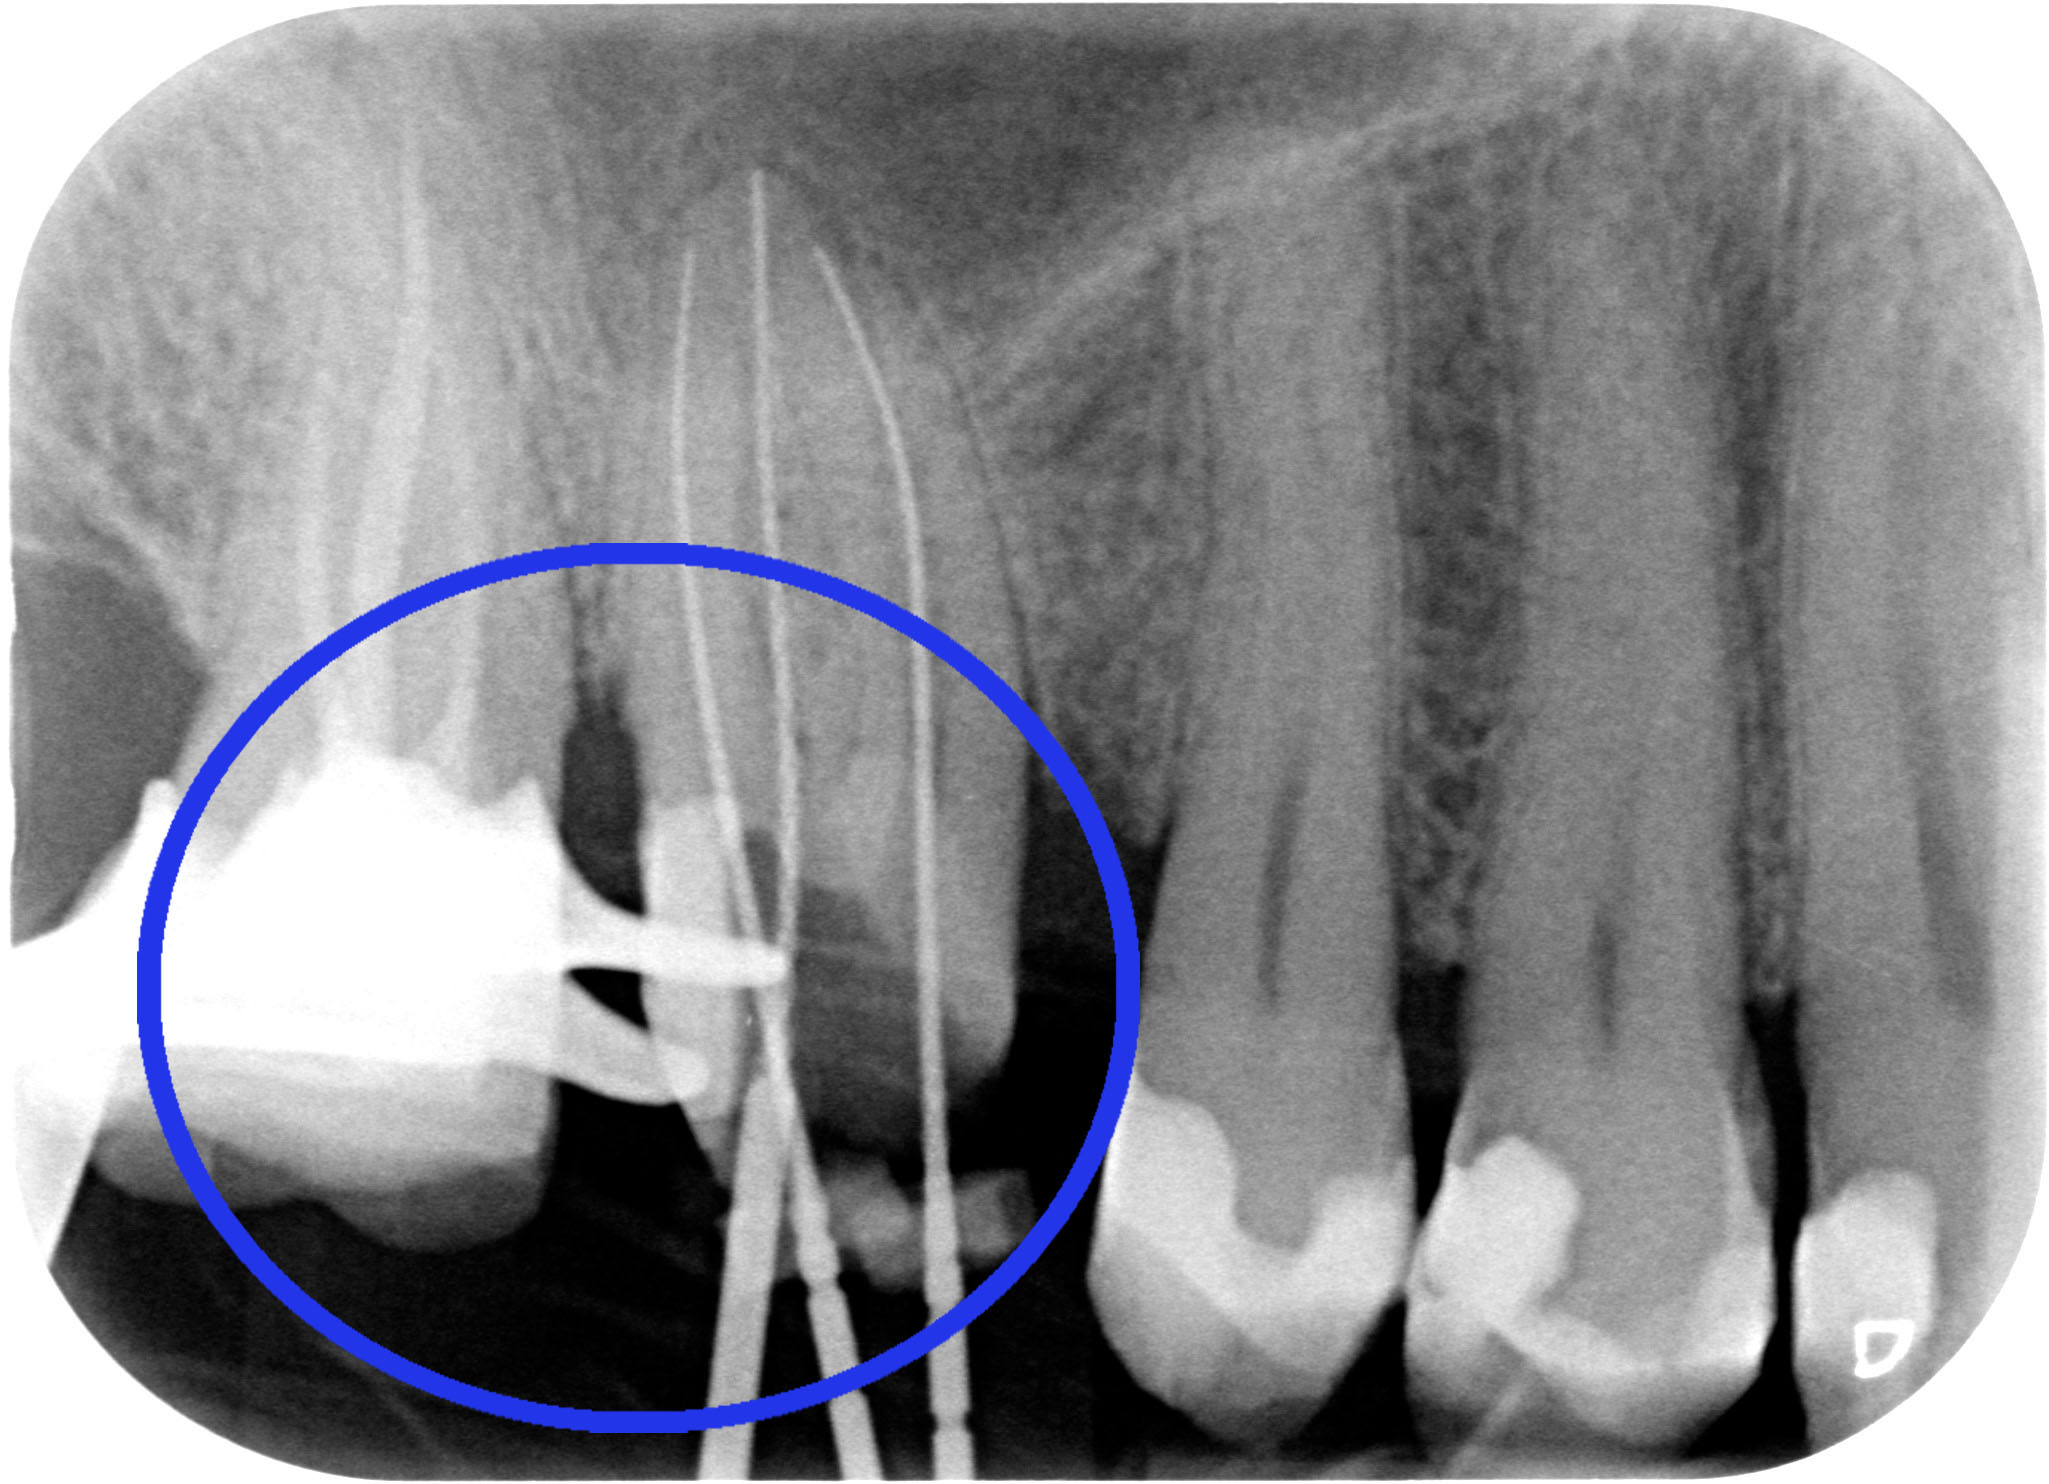

Il riposizionamento apicale dei tessuti parodontali ci consentirà quindi di:

ESEGUIRE UN CORRETTO PRETRATTAMENTO CORONALE

ESEGUIRE UN CORRETTO RITRATTAMENTO CANALARE ISOLANDO IL CAMPO CON LA DIGA DI GOMMA

ESEGURE UN CORRETTO RESTAURO PROTESICO

“Hei hei guarda un po’ lì cosa ha combinato questo?! Una tacca sul dente dietro!!”

Beh caro amico, la fresa tra i due denti ci deve passare e se le due radici sono troppo vicine bisogna creare lo spazio per una papilla interdentale sana e non sofferente, dove poter mettere un filo retrattore (anzi due) alla presa dell’impronta. Quindi sì, lo ammetto: una tacca di qua e una tacca di là!